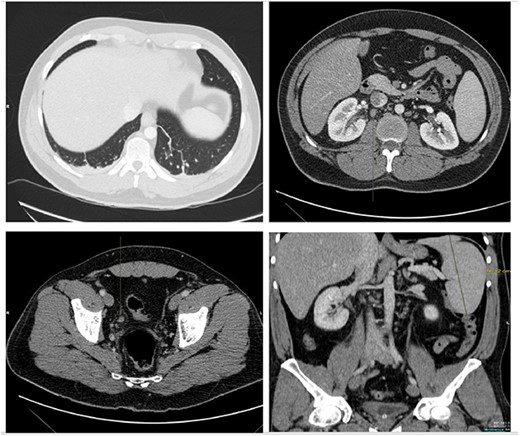

The patient was treated with IV piperacillin-tazobactam. However, he continued to have febrile temperature spikes. No growth was initially detected on blood cultures. The patient developed shortness of breath and respiratory alkalosis, for which a CT pulmonary angiography was done to exclude pulmonary embolism. Only dependent bilateral changes in the lower lobes and signs of mild pulmonary venous congestion were reported (Fig. 3). He was started on hydrocortisone, ethambutol, pyridoxine and rifampicin as empirical treatment for BCGosis. Hydrocortisone was eventually tailored down to prednisolone. Virology tests including hepatitis and immunodeficiency virus were run and these were negative. He continued spiking high temperatures and a repeat CT abdomen with IV contrast was performed which was largely unchanged from the previous scan (Fig. 4). An echocardiogram ruled out infective endocarditis. Incidentally he was in contact with a COVID-19 positive patient and was placed under quarantine for 14 days. Fortunately, he never developed COVID-19 infection. Another CT pulmonary angiography was performed in view of persisting shortness of breath but only mosaic attenuation in the lungs was present.

A repeat CT abdomen with IV contrast was performed which was largely unchanged from the previous scan, save for mild pericholecystic fluid.